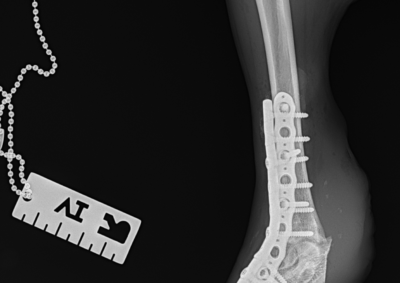

整形外科 注意 ボタンをクリックした先に、治療中および手術中の画像が説明で使用されている場合がございます。 そのような画像に弱い方は閲覧なさらないようお願いいたします。 整形外科 上腕骨外顆骨折の癒合不全 整形外科 大腿骨遠位開放および粉砕骨折 整形外科 膝蓋骨内方脱臼+前十字靭帯断裂 PGR#21+CBLO #251 整形外科 犬の前十字靭帯断裂に対するCBLO #250 整形外科 脛骨粉砕骨折 整形外科 内側鉤状突起分離症(Fragmented Medial Coronoid Process:F... 整形外科 股関節全置換術(トータル・ヒップ・リプレイスメント)#27 整形外科 橈骨固定術 #268 整形外科 橈骨固定術 #267 整形外科 橈骨固定術 #266 整形外科 股関節脱臼に対するBUSTOR #67 整形外科 脛骨粗面剥離骨折 <1234567> 症例カテゴリー 放射線治療整形外科軟部組織外科脳神経外科内科腫瘍外科救急・集中治療リハビリテーション科腫瘍内科内視鏡科脳神経科呼吸器外科中医・漢方猫の腎移植循環器科